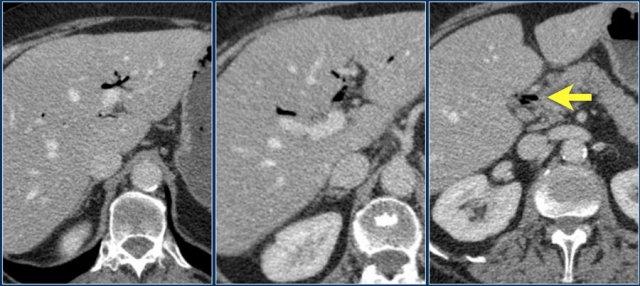

Tăng áp lực tĩnh mạch cửa là một nguyên nhân khác gây ra dấu hiệu bia nước.

Khi bệnh nhân bị tăng áp lực tĩnh mạch cửa, áp lực tăng cao sẽ được truyền đến đại tràng phải.

Điều này dẫn đến sự sản sinh các chất trung gian gây viêm và tăng sản xuất nitric oxide, gây tổn thương mô.

Hậu quả là xuất hiện viêm đại tràng khu trú ở bên phải.

Hãy phân tích các hình ảnh trước khi tiếp tục đọc.

Các dấu hiệu bao gồm:

- Xơ gan – bờ gan không đều

- Giãn tĩnh mạch và lách to

- Cổ trướng

- Viêm đại tràng bên phải

- Phình động mạch gan

Chẩn đoán phân biệt bao gồm:

- Tăng áp lực tĩnh mạch cửa

- Viêm đại tràng nhiễm khuẩn

- Viêm đại tràng thiếu máu cục bộ

Viêm đại tràng bên phải ở bệnh nhân xơ gan và tăng áp lực tĩnh mạch cửa. Hình ảnh nội soi là của bệnh nhân khác có viêm đại tràng bên phải.